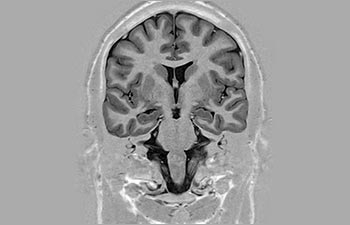

Enhanced diagnostic confidence in neuro oncology

Find the right clinical applications for your needs